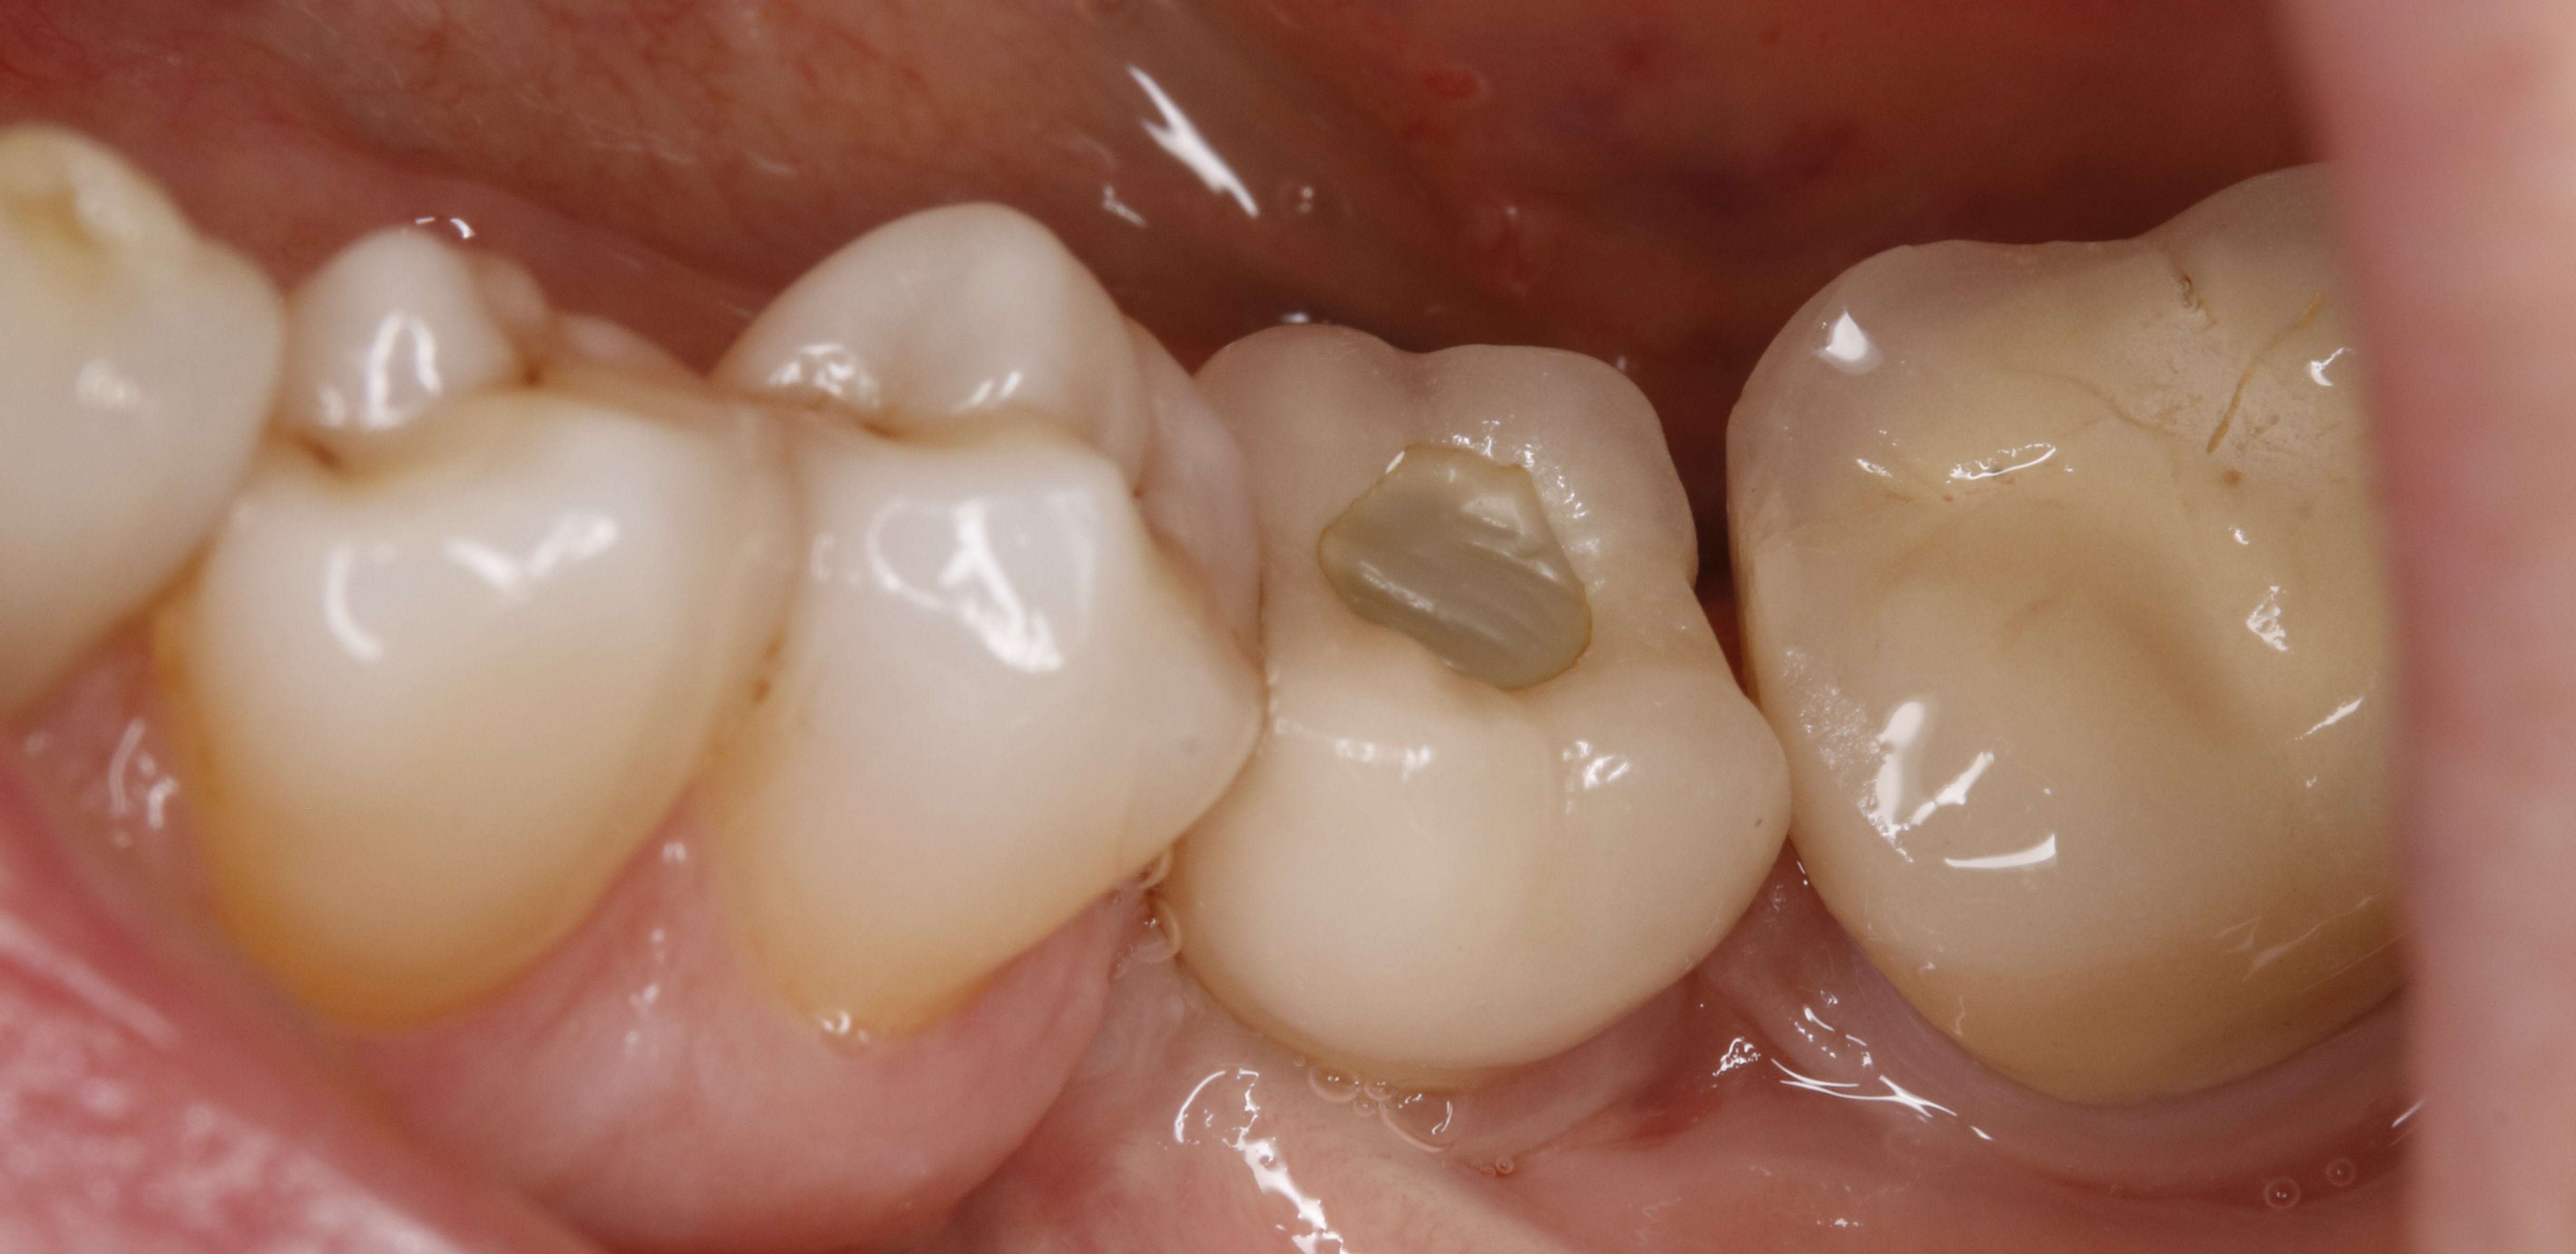

lardonbis écrivait:

---------

" la 24 c'est quoi ? "

ç est une photo au miroir , donc je suppose que tu demandes : la 14 ç est quoi ?

ben la voilà